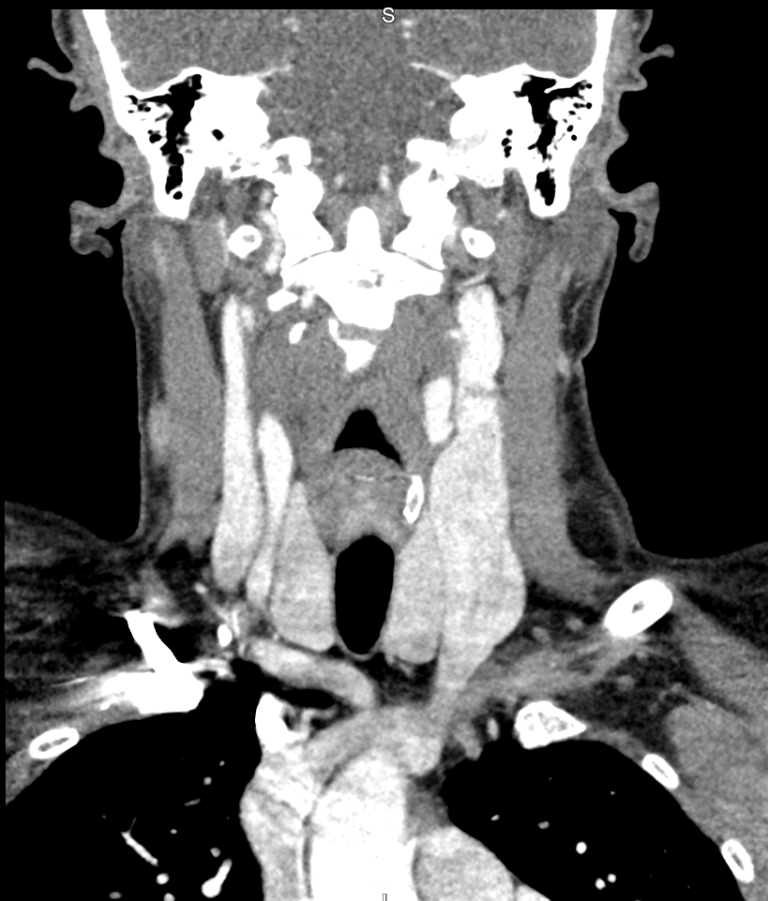

Na tomografia de pescoço com uso de contraste, são analisadas as estruturas vasculares da região estudada. A solução de contraste iodado é administrada por via endovenosa e distribui o contraste entre as estruturas com fluxos sanguíneos, realçando as estruturas hipervascularizadas, mostrando, por exemplo, tumores ou processos inflamatórios.